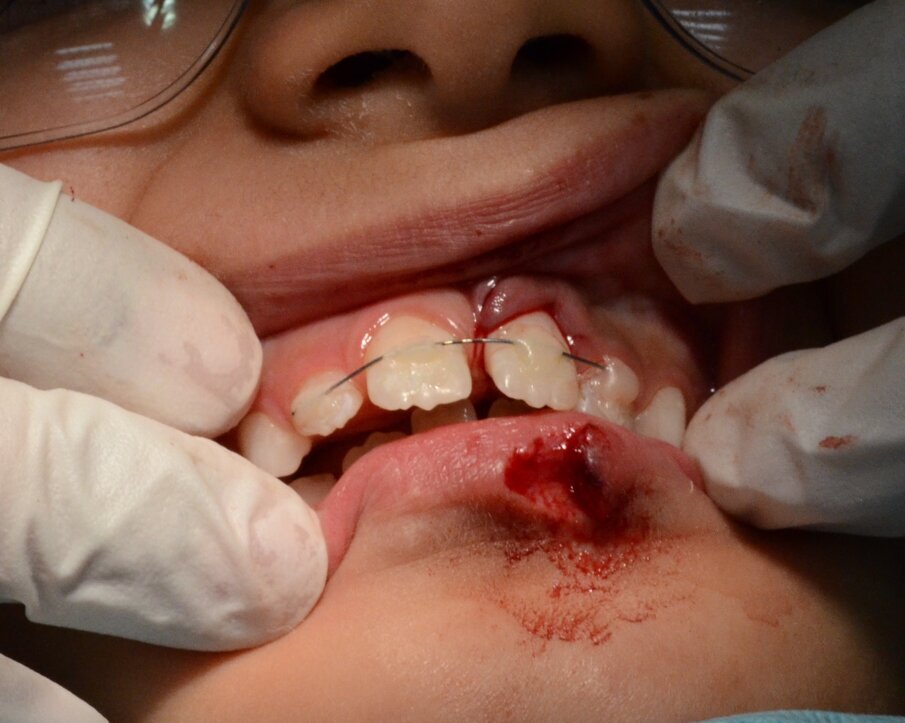

Within the hour, tooth 21 was gently replanted into the socket (Figure 6) and a flexible 0.5mm wire/composite passive splint of teeth #12, 11, 21, 22 was secured (Figure 7). We sutured the lacerated lower lip in multiple layers (mucosa, deep and superficial) using Vicryl® (Sizes 40 and 60) resorbable fine sutures (Figure 8 and 9). This took place after thorough debridement of the wound with physiological saline. Care was taken to assure alignment of the lip’s vermilion involved in the laceration.

Figure 7. A passive composite and wire splint involved # 12 to 22. The lip was yet unsutured.

Figure 8. Suturing of the lower lip laceration in three layers using fine resorbable sutures (Vicryl® Sizes 40 and 60).